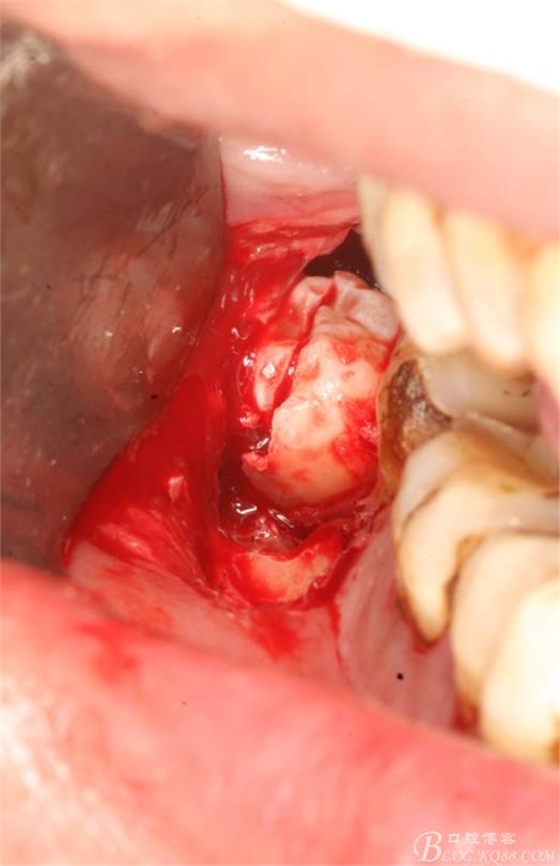

6.橫斷牙冠

7.取出牙冠